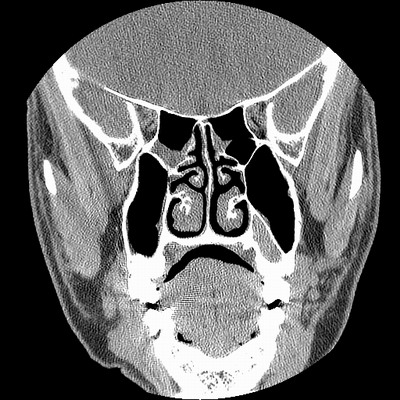

男,38岁,鼻塞、头痛2个月,要求鼻窦ct检查。

右侧上颌窦、蝶窦、筛窦、额窦及左侧上颌窦慢性炎症。

右侧鼻中隔左偏,右侧上颌窦、筛窦、额窦慢性炎性病变。右侧上颌窦开口粘膜增厚。

1)副鼻窦炎。2)右侧中鼻道及总鼻道粘膜息肉样变。3)双侧中下鼻甲肥大。4)鼻中隔轻度左突偏曲。